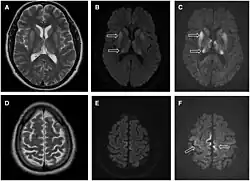

MR-scanning af hjernen kan anvendes til non-invasiv diagnostik. Stærkt signal på T2-sekvenser i nuclei pulvinares indikerer vCJD (høj sensitivitet og specificitet). Radiologiske tegn på sCJD er bl.a. stærkt signal på diffusionsvægtet MR i nucleus caudatus og putamen og evt. cortex cerebri, men disse har dog lavere sensitivitet end tegnene for vCJD.[4]